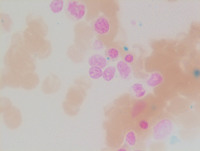

Figure 2: Bone marrow aspirate

Aspirate smears are cellular and demonstrate increased numbers of blasts accounting for 31% of all cells. The blasts are small to medium in size with scant to moderate basophilic cytoplasm, round nuclear contours, fine chromatin and prominent nucleoli (Black arrow-Top left image). Erythroid precursors show megaloblastoid maturation with occasional erythroid precursors demonstrating nuclear irregularities consistent with dysplastic changes. Several dysplastic micromegakaryocytes, frequently with hypolobated and widely separated nuclei are noted (White arrow-Top right image). Additionally, occasional dysplastic megakaryocytes exhibiting "pawn-ball" cytomorphology are seen (Green arrow-Bottom image). Such pawn-ball megakarytocytes are often described in patients with germine GATA2 mutations.